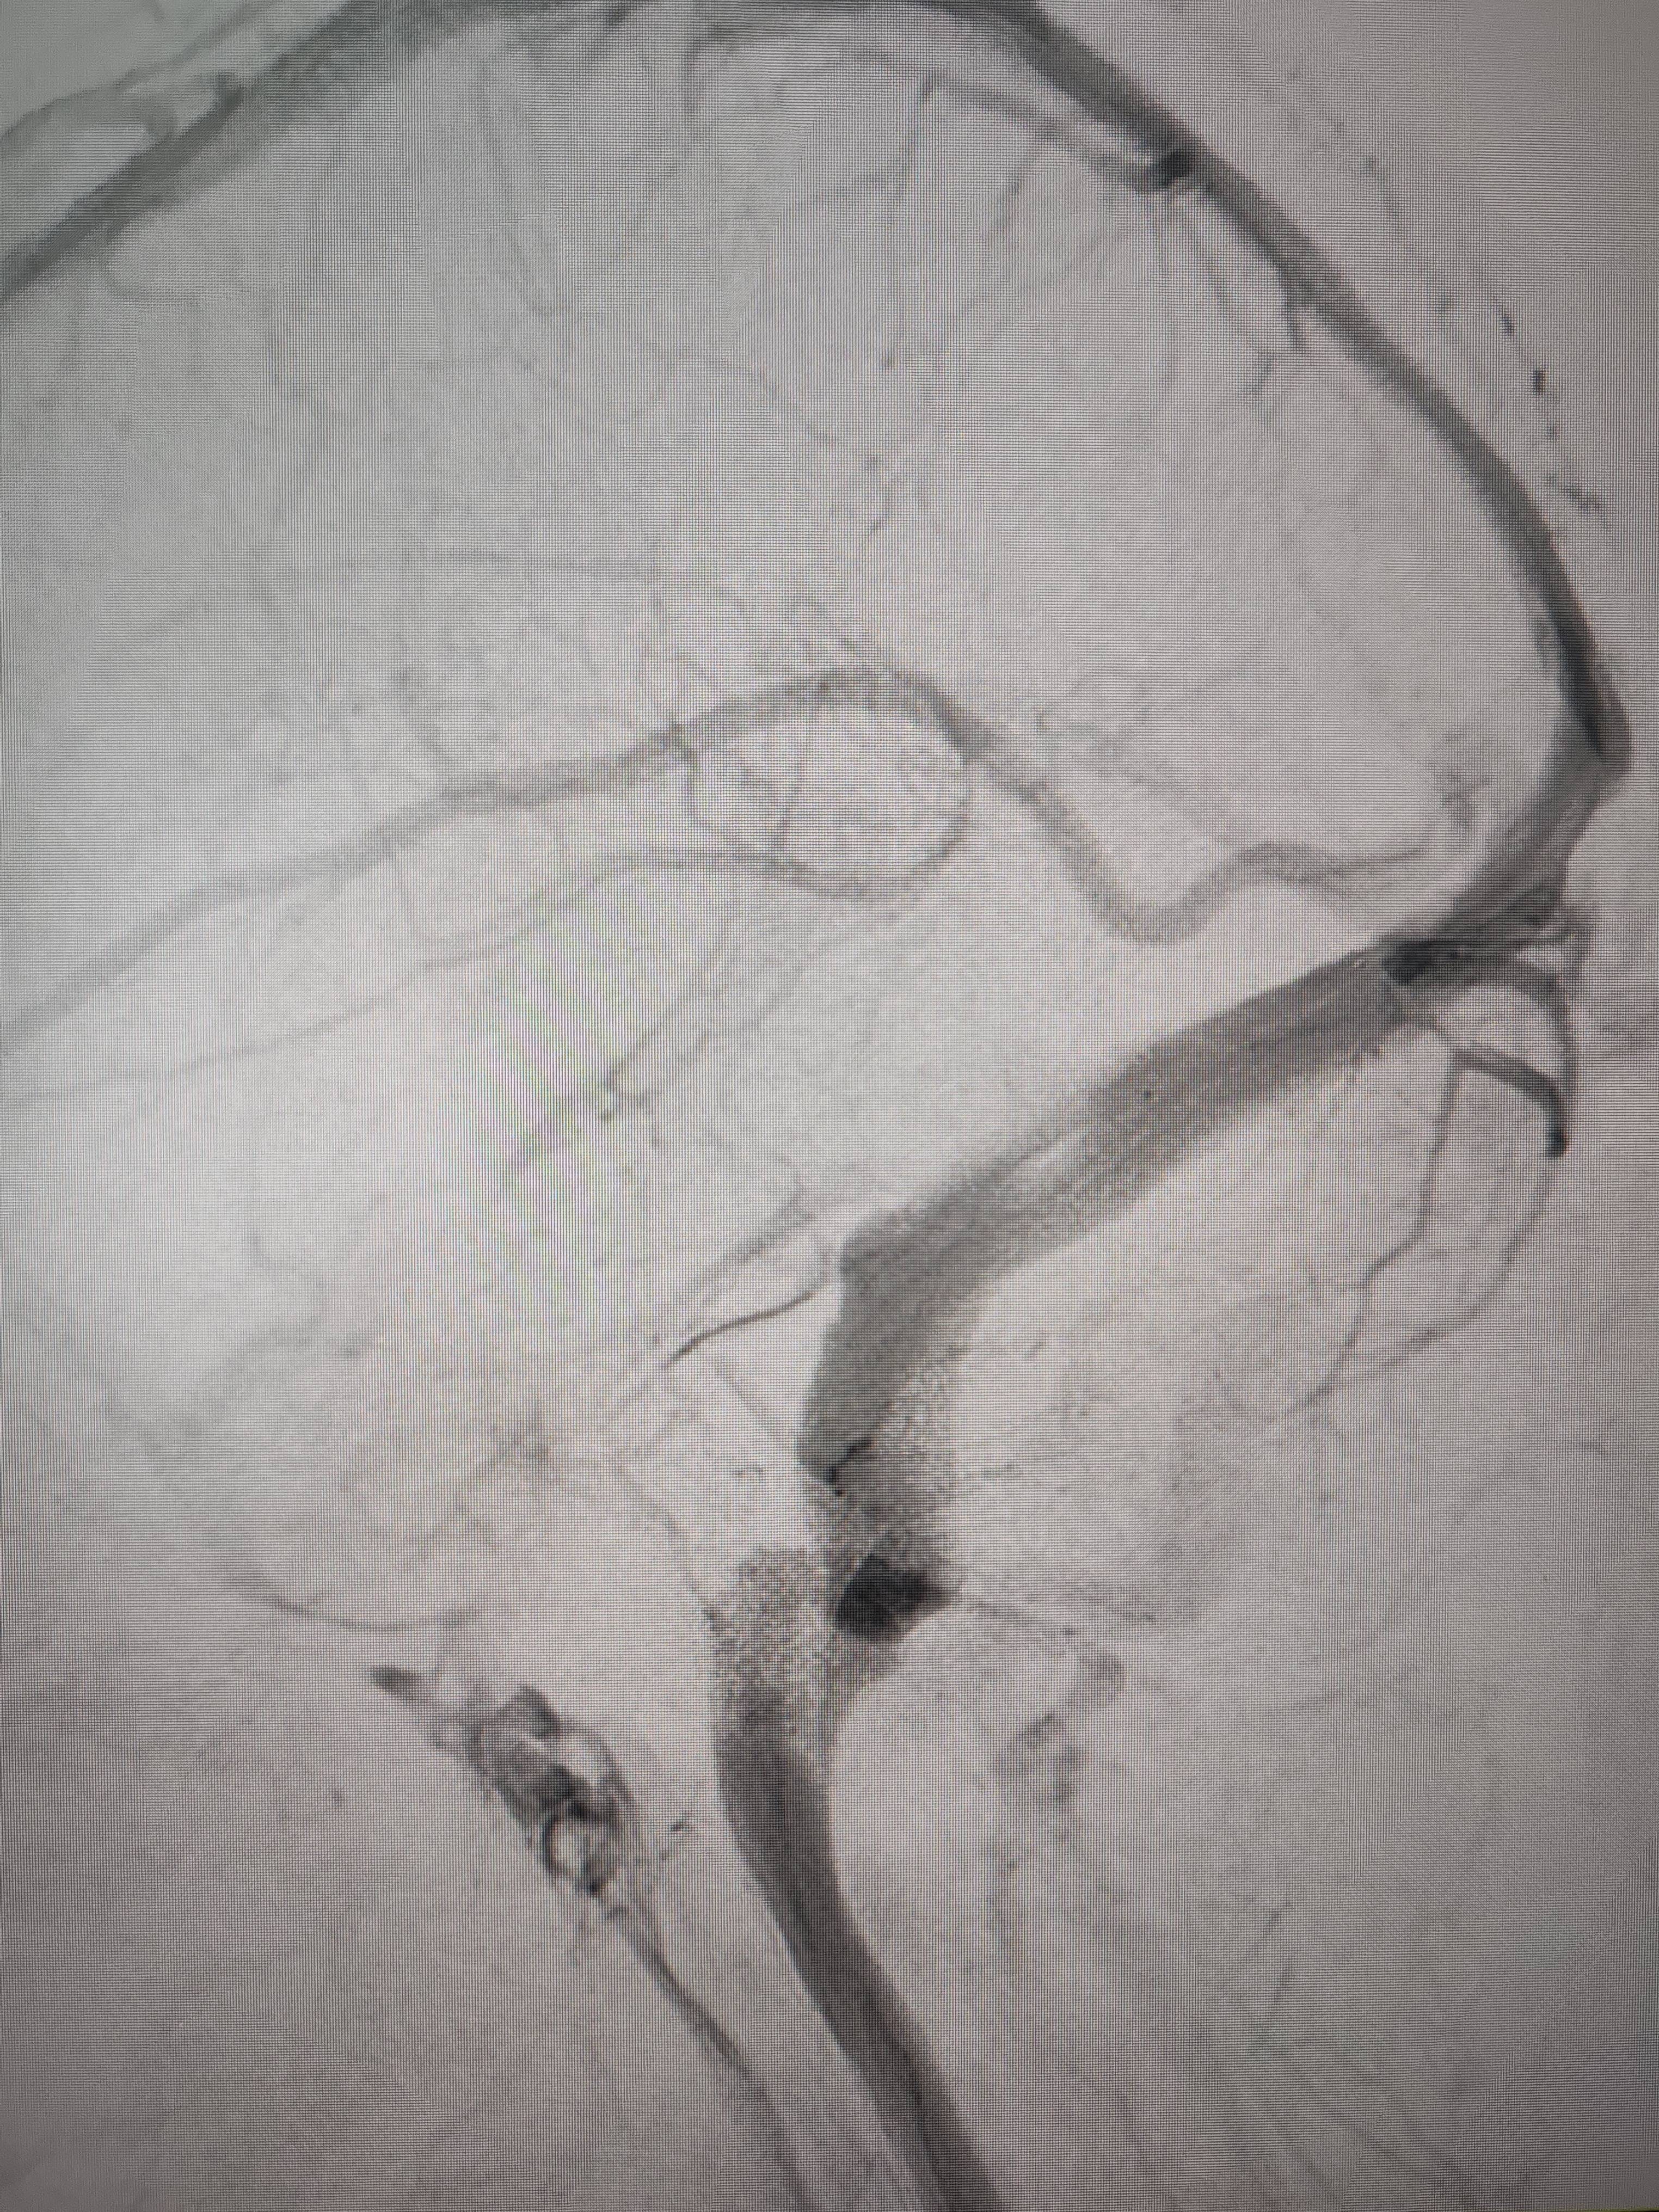

经过静脉窦支架置入手术治疗后,患者的静脉窦“堵点”被打通理财学。 南方+ 欧阳少伟 拍摄

“从手术室出来,麻药清醒以后,我感觉整个世界都清静了,没想到效果这么立竿见影理财学。”减轻病痛的赵女士,术后很是开心,次日就可下床自如活动,目前已康复出院。